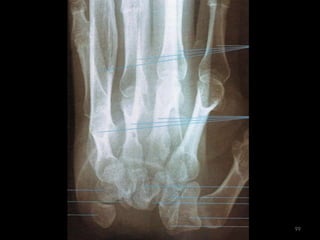

Incidência PA Mão118

119

120

Incidência oblíqua PA da mão125

126

127